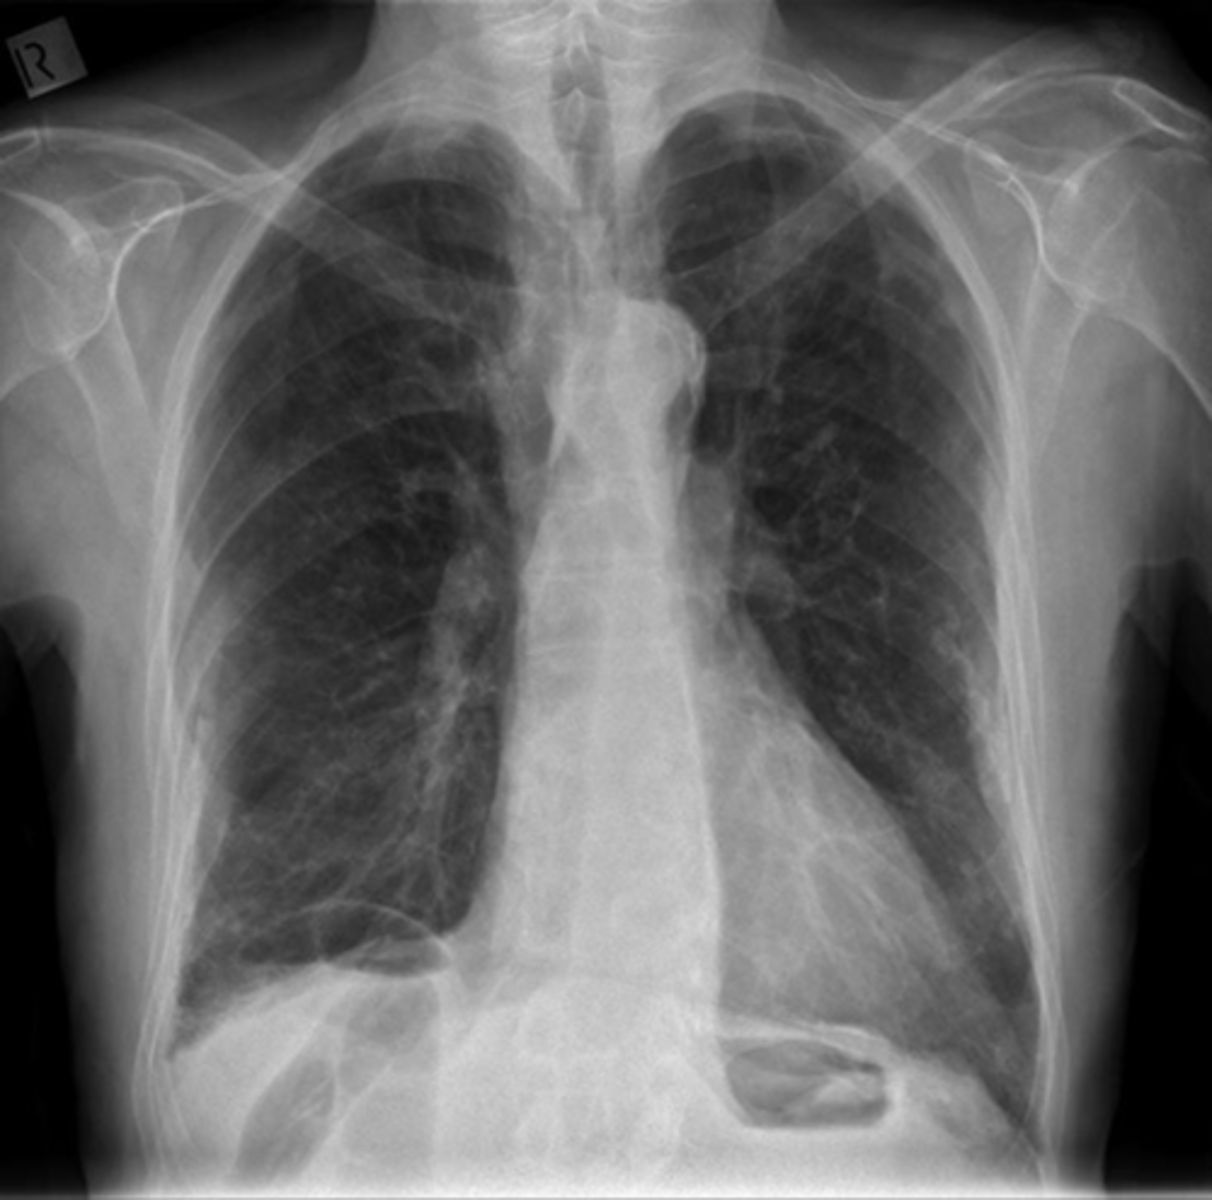

NORMAL LIVER ANATOMY

DOTTED BLACK ARROW:

Ligamentum teres - divides the left love of the liver into medial and latera segments, with larger right lobe more posterior.

M: Medial segment of left lobe

L: Lateral segment of left lobe

R: larger right lobe of liver.

PV: Portal vein, lying just posterior to the hepatic artery

SOLID BLACK ARROW: hepatic artery

SOLID WHITE ARROW: Splenic artery, follows the path of the pancreas towards the spleen

P: PANCREAS

S: Spleen

IVC: Inferior vena cava, lying right of the aorta

A: Aorta